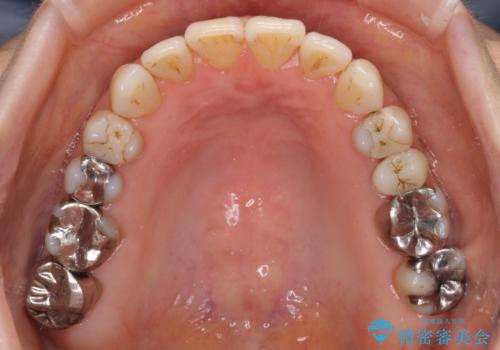

- 前歯の上下スペースと前歯の隙間を気にして来院された患者様です。

インビザラインにより上下の前歯の隙間を閉じながら、IPRを用いて口元の突出感を合わせて改善していくこととしました。

上下の隙間に舌が入り込むことが、すきっ歯やオープンバイトの原因であったため、舌の筋肉のトレーニングも並行して行い、後戻りの抑制を図りました。